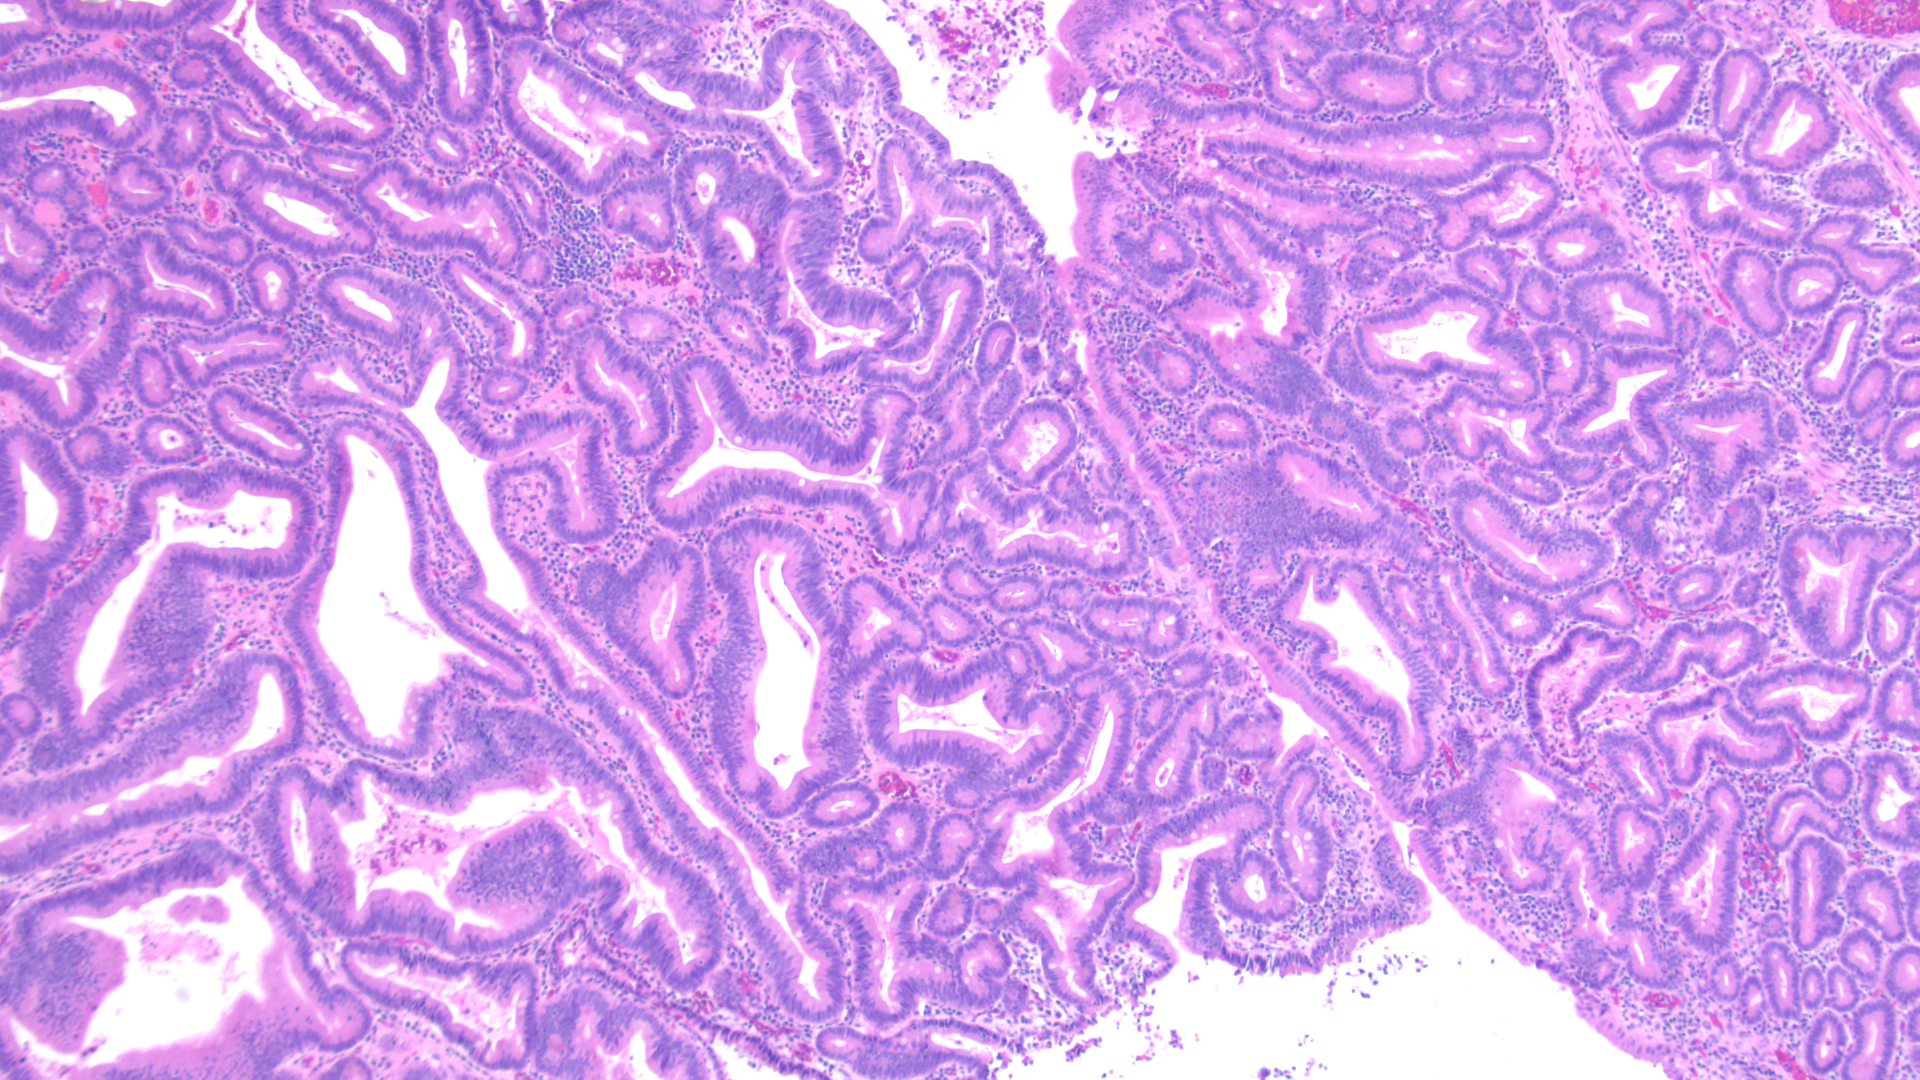

Tissue track samples resulted in the diagnosis of ampullary adenoma without evidence of high-grade dysplasia (Figures 4,5), and cytology from the brush biopsy showing atypical glandular cells. CA 19-9 levels decreased from 152 to 25 units/ml one month post-procedure. Due to a diagnosis of ampullary adenoma, the patient and her family were counseled on ampullectomy to prevent ampullary cancer versus watchful waiting. They elected to pursue ampullectomy. The procedure was performed under general anesthesia. A side viewing duodenoscope was advanced to the second part of the duodenum. The previously placed biliary stent was retrieved using a snare.  The scope was then repositioned to visualize a large 3.5 cm ampullary adenoma (Fig 1). Cholangioscopy (spyglass Boston Scientific) also revealed possible skip lesions versus changes from the prior stent in the bile duct.  Submucosal injection was then performed and the lesion lifted from the wall showing that it was not fixed to the side of the duodenum.  A 27 mm Captivator snare was used to perform ampullectomy which was retrieved using a Roth net.  A residual lesion on the margin was removed using a 15 Captivator, also retrieved using a Roth net.  After ampullectomy, cannulation of the pancreatic duct was achieved using Jagwire Revolution (Boston Scientific), after which a 5 cm French single pigtail pancreatic stent was placed.  The bile duct was also cannulated, after which double-pigtail 7 cm 10 French plastic biliary stent was placed with good biliary drainage (Figures 2,3).  Margins were ablated using Argon plasma coagulation to prevent adenoma recurrence. Histopathology showed intestinal type ampullary adenoma with low grade dysplasia and no invasive adenocarcinoma (Figures 6,7). One month later, ERCP was conducted during which both the double and single pigtail stents were removed, and further interrogation of the bile duct with cholangioscopy revealed no skip lesions suggesting that the observed small changes were due to the previous metal stenting. A 60mm x 10mm self-expanding metal biliary wall stent (Boston Scientific) was placed with good biliary drainage. The patient tolerated both procedures well without any adverse event.

Figure 4 - Initial ampullary biopsy, 40x magnification

Figure 5 - Initial ampullary biopsy, 100x magnification